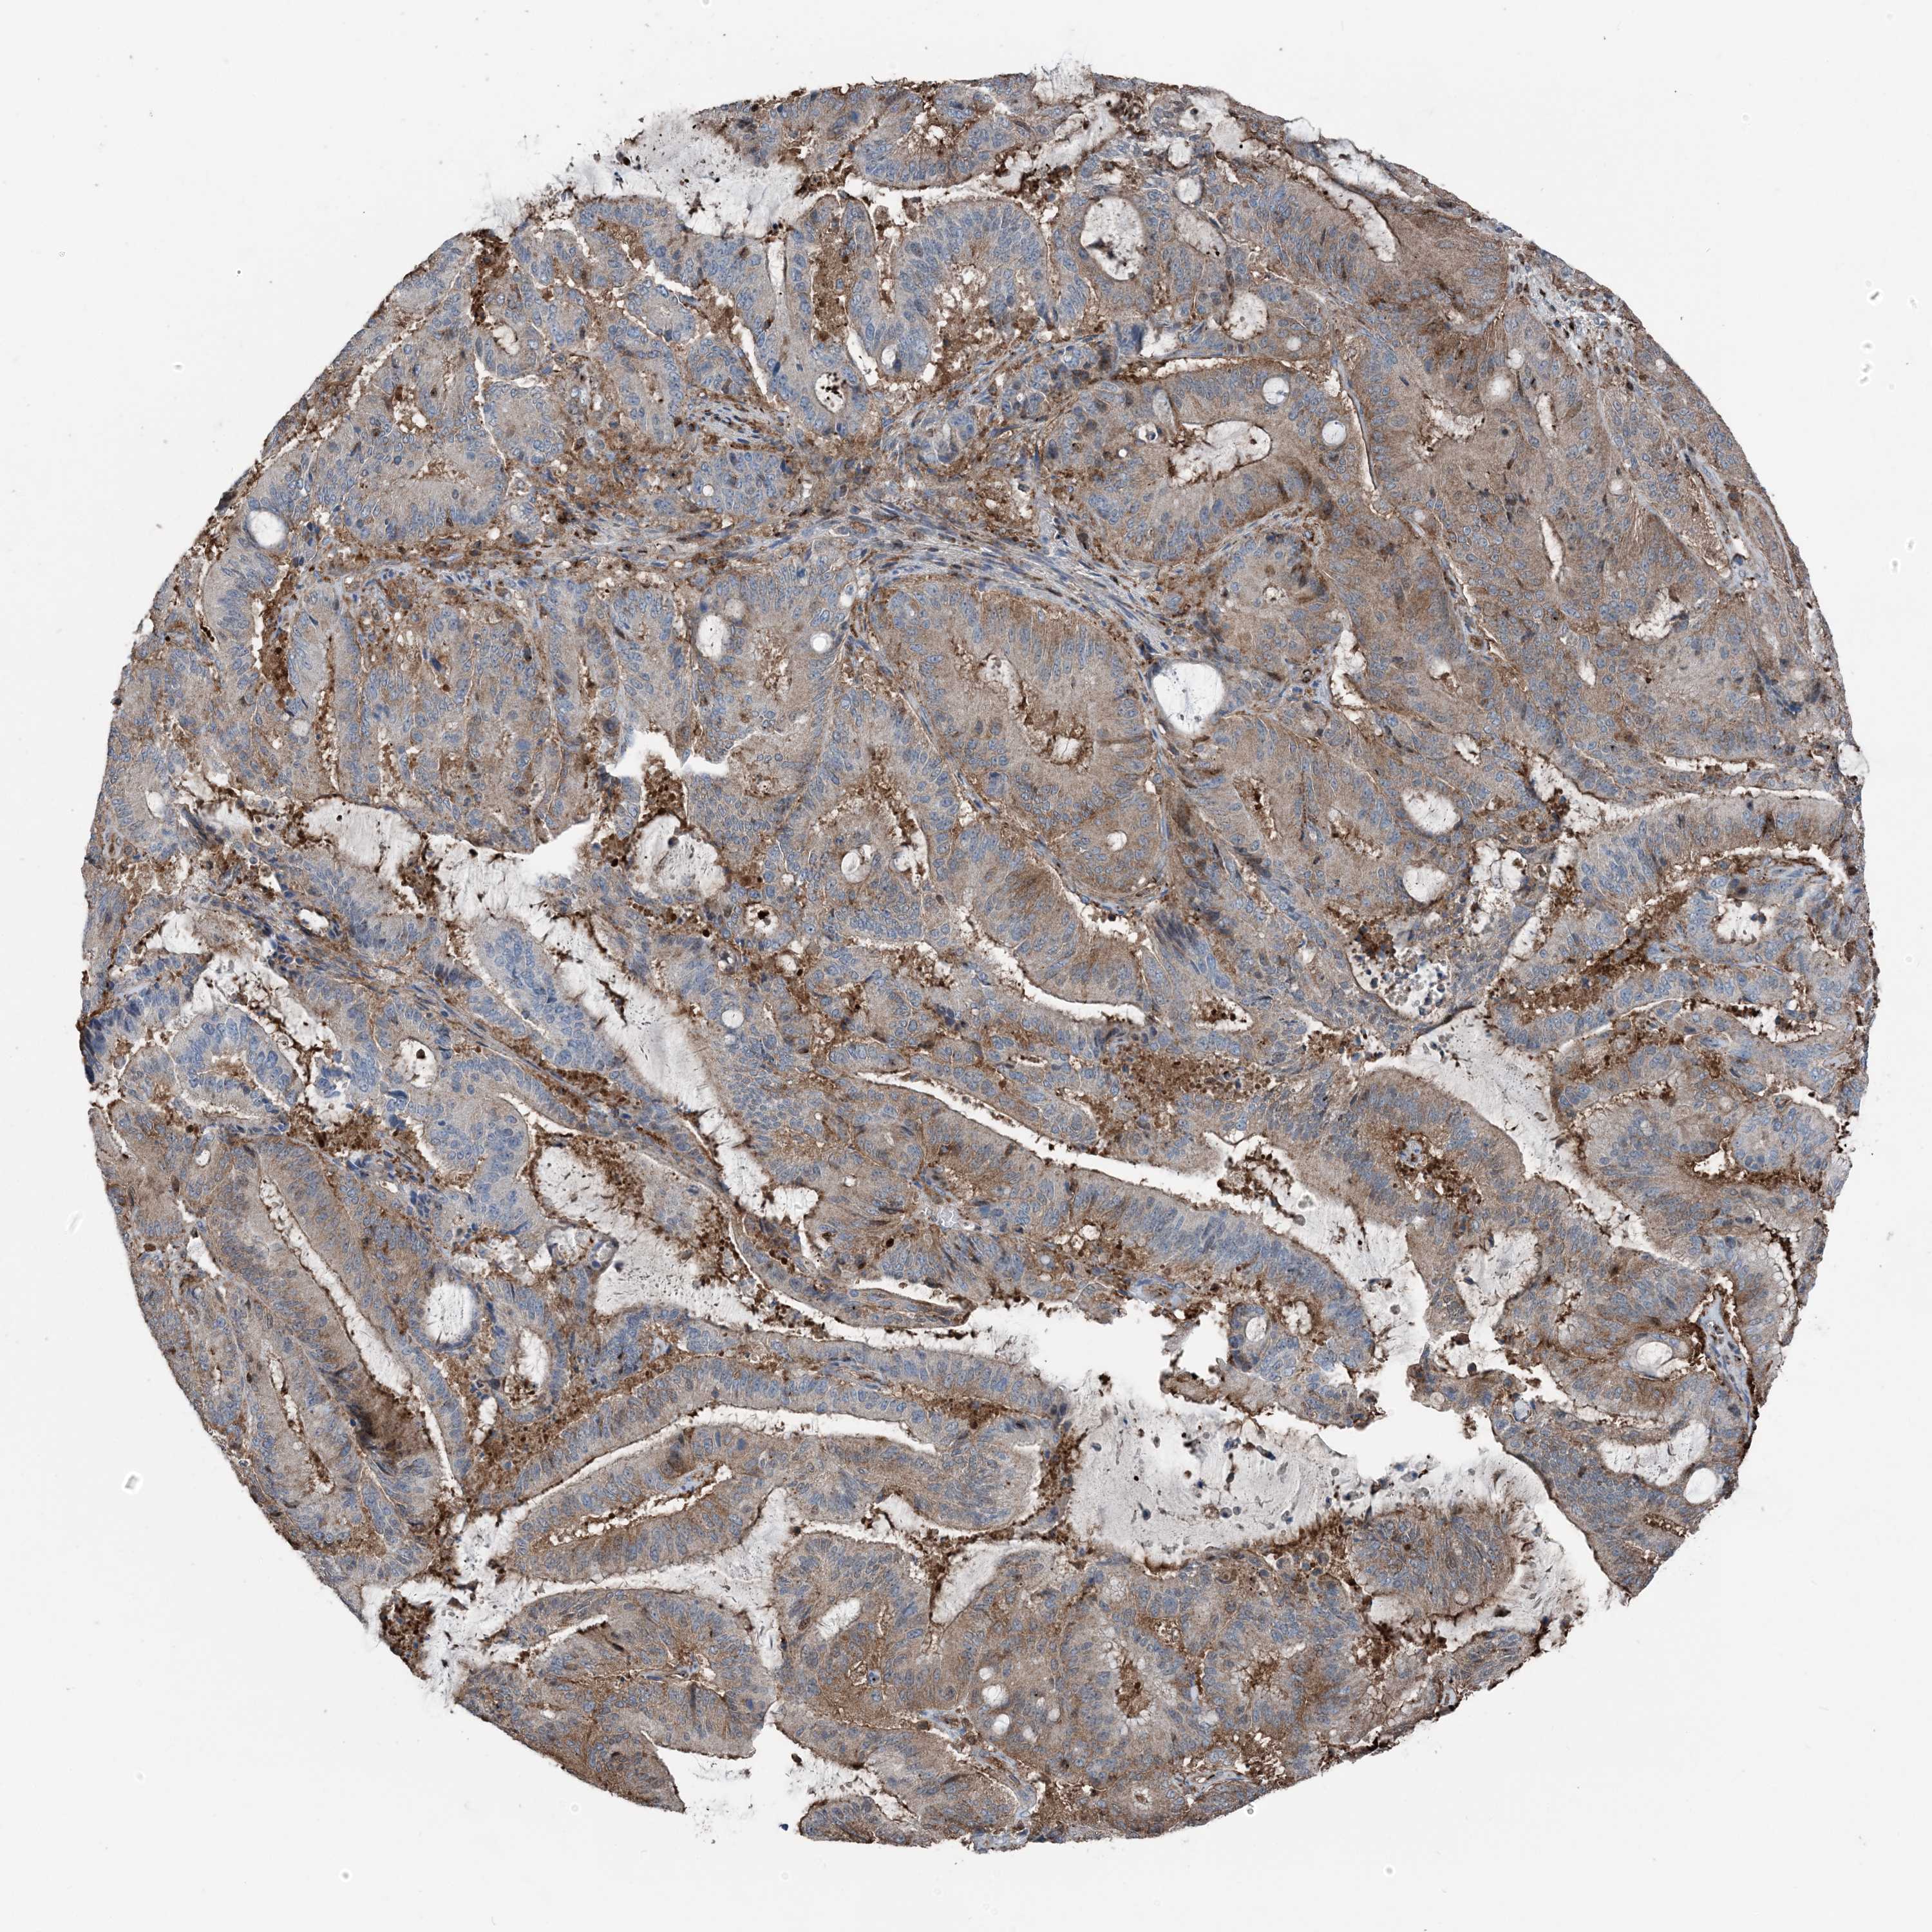

LIVER CANCER - Protein expressioni

A mouse-over function shows sample information and annotation data. Click on an image to view it in a full screen mode. Samples can be filtered based on level of antibody staining by selecting one or several of the following categories: high, medium, low and not detected. The assay and annotation is described here.

Note that samples used for immunohistochemistry by the Human Protein Atlas do not correspond to samples in the TCGA dataset.

Antibody stainingi

Antibody staining in the annotated cell types in the current human tissue is reported as not detected, low, medium, or high, based on conventional immunohistochemistry profiling in selected tissues. This score is based on the combination of the staining intensity and fraction of stained cells.

Each image is clickable and will lead to virtual microscopy that enables deeper exploration of all samples and also displays staining intensity scores, fraction scores and subcellular localization as well as patient and tissue information for each sample.

Antibody HPA053761

Cholangiocarcinoma

Carcinoma, Hepatocellular, NOS